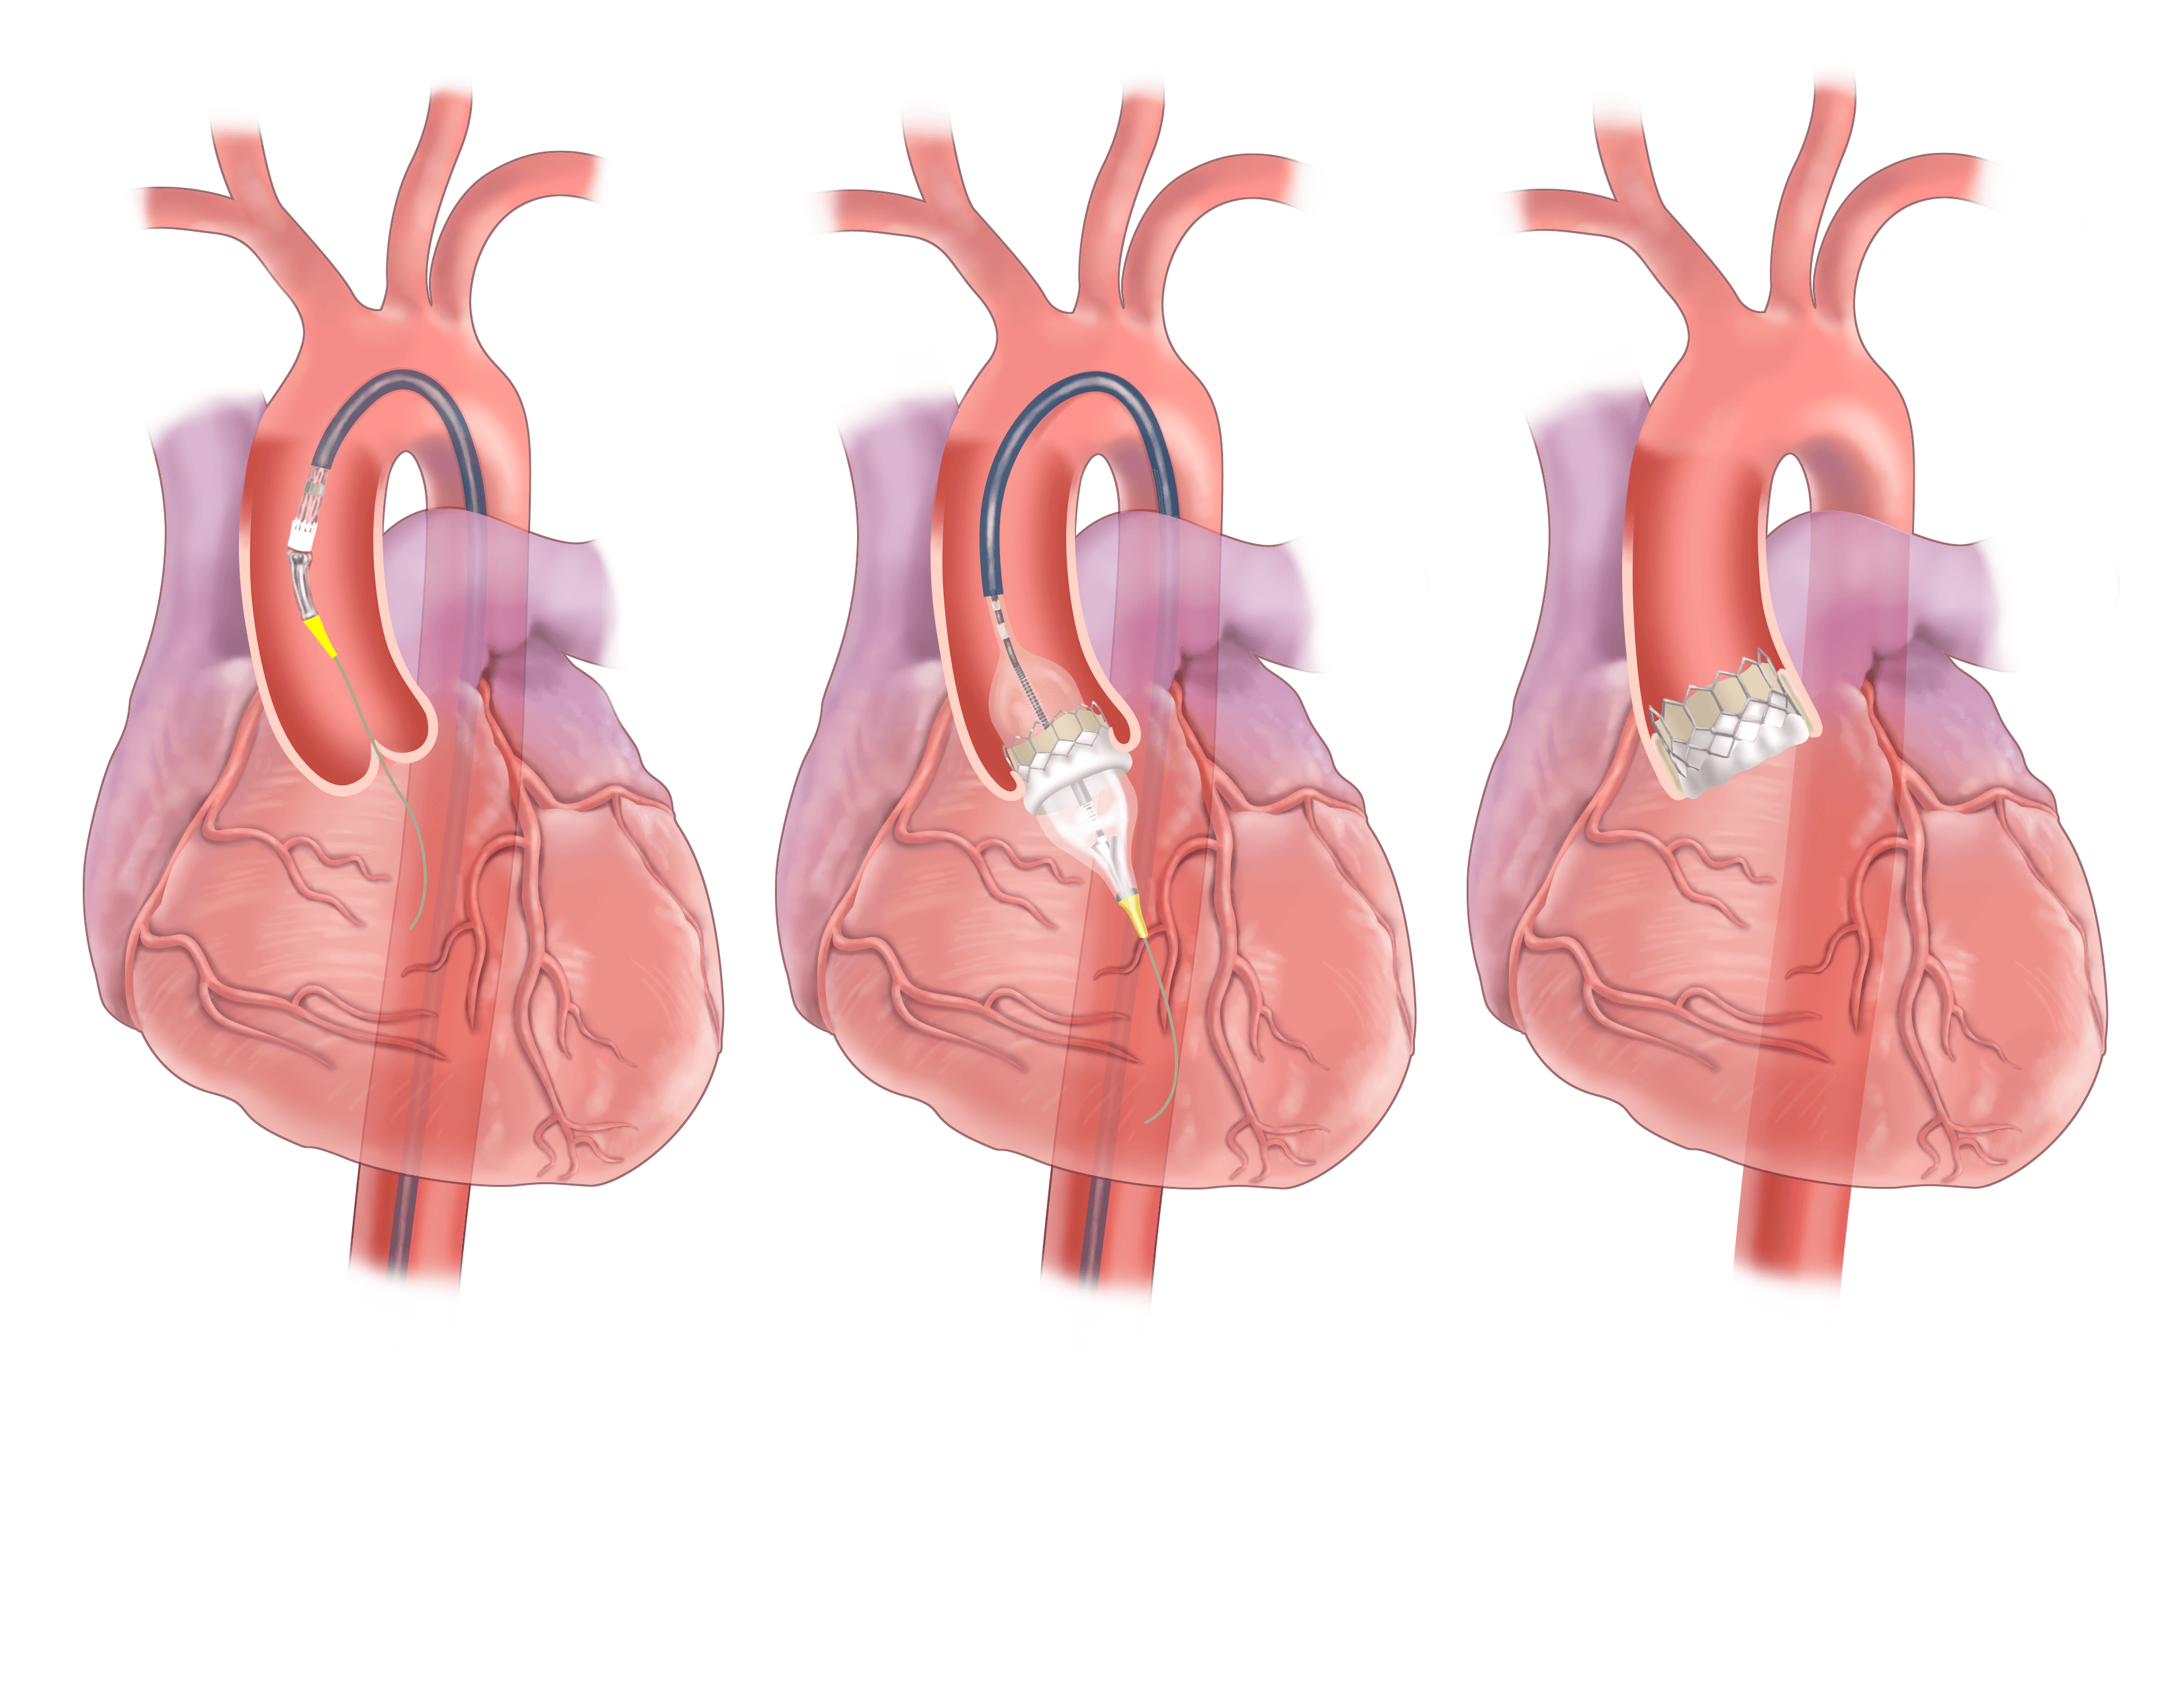

Overview

Package includes:

Days in hospital : 7 to 8 Days (For patient and one attendant)

Days in hotel : 14 Days (For patient and one attendant)

Room type in hospital : Shared

Room type in hotel : Private

Hotel category: General

Value added benefits of the Double Valve Replacement and CABG:

Overview

Package includes:

Days in hospital : 7 to 8 Days (For patient and one attendant)

Days in hotel : 12 Days (For patient and one attendant)

Room type in hospital : Shared

Room type in hotel : Private

Hotel category: General

Value added benefits of the Mitral Valve Replacement:

Overview

Package includes:

Days in hospital : 7 to 8 Days (For patient and one attendant)

Days in hotel : 12 Days (For patient and one attendant)

Room type in hospital : Shared

Room type in hotel : Private

Hotel category: Standard

Value added benefits of the Aortic Valve Replacement:

Overview

Package includes:

Days in hospital : 7 to 8 Days (For patient and one attendant)

Days in hotel : 14 Days (For patient and one attendant)

Room type in hospital : Shared

Room type in hotel : Private

Hotel category: Standard

Value added benefits of the Double Valve Replacement:

Overview

Package includes:

Days in hospital : 7 to 8 Days (For patient and one attendant)

Days in hotel : 14 Days (For patient and one attendant)

Room type in hospital : Shared

Room type in hotel : Private

Hotel category: Standard

Value added benefits of the Single Valve Replacement:

Overview

Package includes:

Days in hospital : 7 to 8 Days (For patient and one attendant)

Days in hotel : 14 Days (For patient and one attendant)

Room type in hospital : Shared

Room type in hotel : Private

Hotel category: Standard

Value added benefits of the CABG and AVR:

Overview

Package includes:

Days in hospital : 7 to 8 Days (For patient and one attendant)

Days in hotel : 14 Days (For patient and one attendant)

Room type in hospital : Shared

Room type in hotel : Private

Hotel category: Standard

Value added benefits of the CABG and MVR: